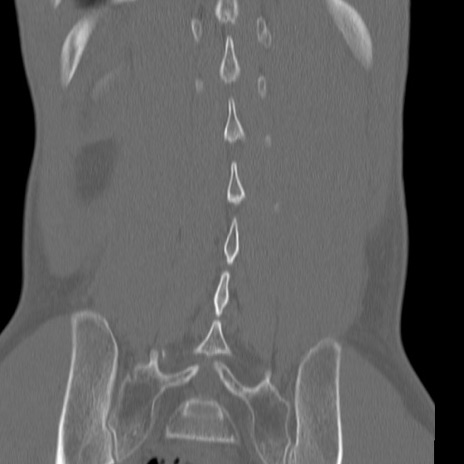

症例3 腰椎CT(冠状断像)

【症例】30歳代男性

【主訴】腰痛

【現病歴】本日旅行先で観光中に、友人と衝突し転倒し受傷。

【身体所見】麻痺なし、右下腿内側前面外側、左下腿内側に知覚鈍麻・しびれ

異常所見と診断は?

3D再構成